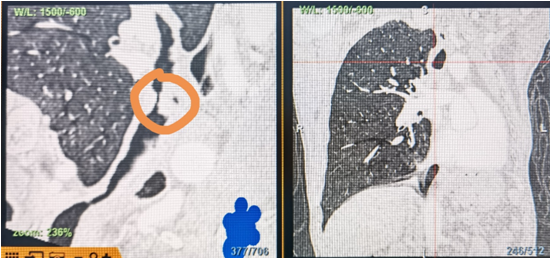

時間就是生命!了解患者病情后,歐陽海峰立刻啟動氣道梗阻緊急救治通道,協(xié)調(diào)院前轉(zhuǎn)運,急診快速入院流程。凌晨患者入院胸部CT顯示,現(xiàn)存唯一的呼吸通道在右主支氣管處,狹窄處僅約3毫米,患者命懸一線!